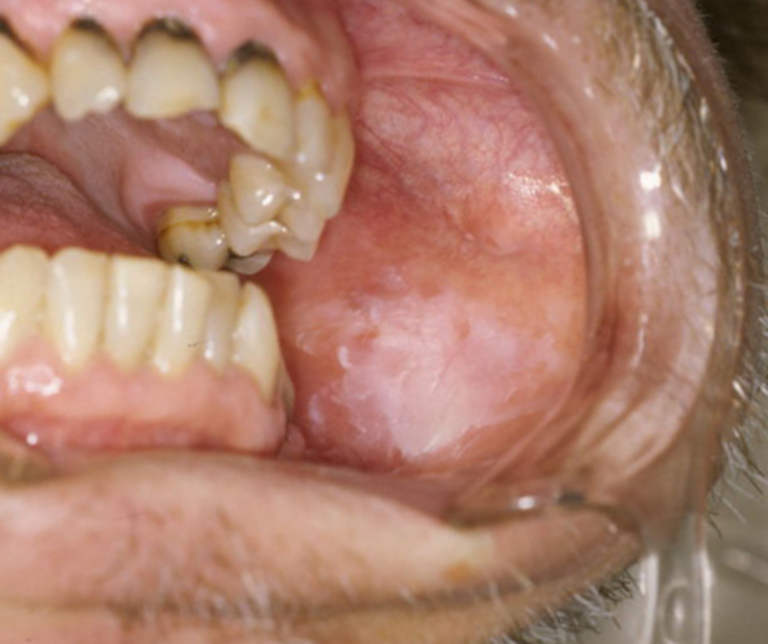

② 口腔粘膜疾患(白板症・扁平苔癬など)

五反田の歯医者、ツツミ歯科クリニックのお口の中のデキモノ

癌ではありませんが、放置すると癌化する可能性がある「前癌病変」や、難治性の炎症です。

これらは定期的な経過観察と、高度な専門知識による「見極め」が非常に重要です。

白板症

粘膜が白くなり、擦っても取れないもの。一部が癌化するリスクがあります。

扁平苔癬(へんぺいたいせん)

レース状の白い模様ができ、食べ物がしみることがあります。